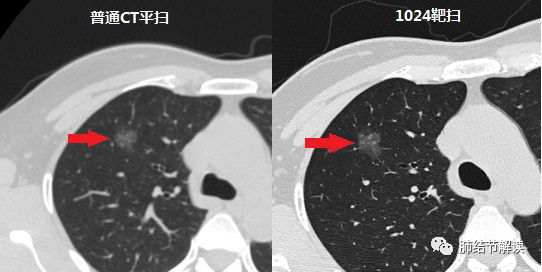

南京市胸科医院有目前国内最先进的胸部CT(1024靶扫),1024扫描为超薄层扫描及重建图像的检查技术,具体来说就是采用最新的超高分辨率CT,进行肺部小结节的数据采集和三维重建。

南京市胸科医院有目前国内最先进的胸部CT(1024靶扫),1024扫描为超薄层扫描及重建图像的检查技术,具体来说就是采用最新的超高分辨率CT,进行肺部小结节的数据采集和三维重建。PPW帝国网站管理系统